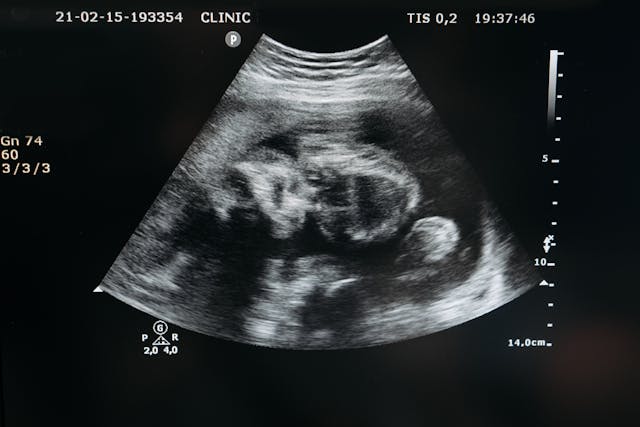

Artificial wombs, devices that can gestate human embryos outside the body, have shifted from speculative fiction to the brink of medical reality.

Artificial womb technology (AWT), once purely fictional, is now entering the domain of biomedicine, with implications for the field of assisted reproductive technologies (ART), including surrogacy, the law on abortion and social inequality.

The science of AWT is real, although limited. Current experiments represent partial ectogenesis: where a foetus begins developing in the uterus and is then transferred to an artificial womb to continue its growth. Scientists in the Unites States, the Netherlands, and Japan have sustained premature animal foetuses in external ‘biobags‘.

Full ectogenesis (a baby never incubated in a human womb) may still be decades away, dependent on breakthroughs in placental bioengineering, infection control, and safely initiating embryo growth outside the uterus.